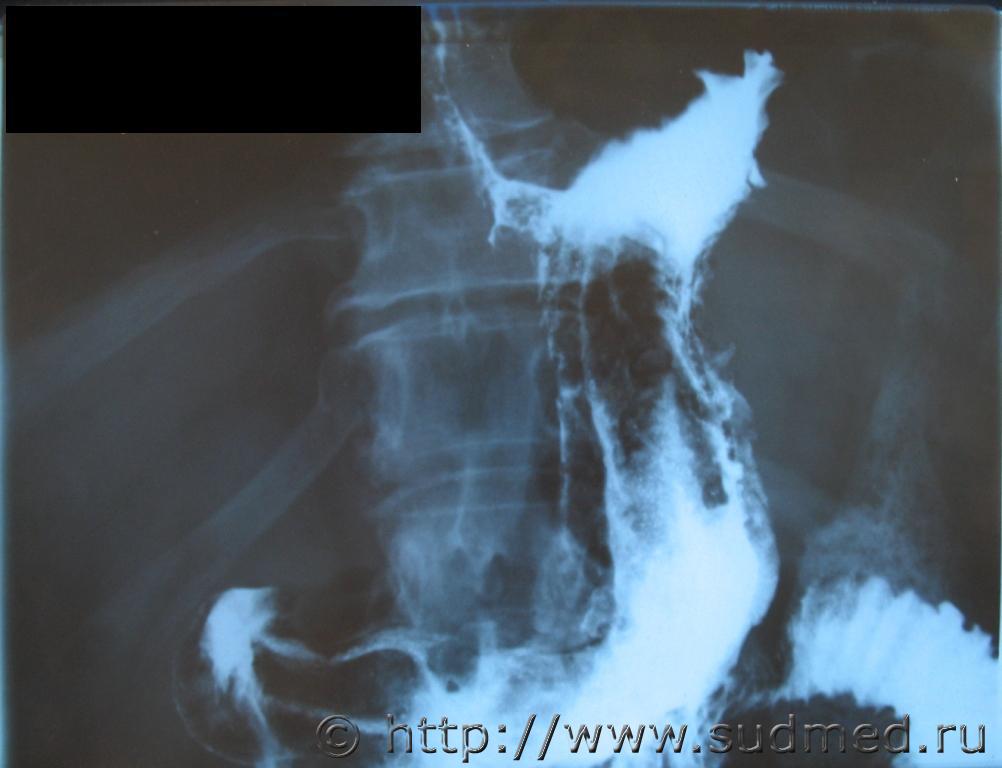

Женщина,53 лет,обратилась за медпомощью в поликлинику.Рентгенологически и эндоскопически рак желудка не диагностирован.До госпитализации в стационар не дожила.

Фото 1.Рентгенограмма.

Фото 2.Диффузный тотальный рак желудка (пластический линит).

Фото 3.Метастазы рака.